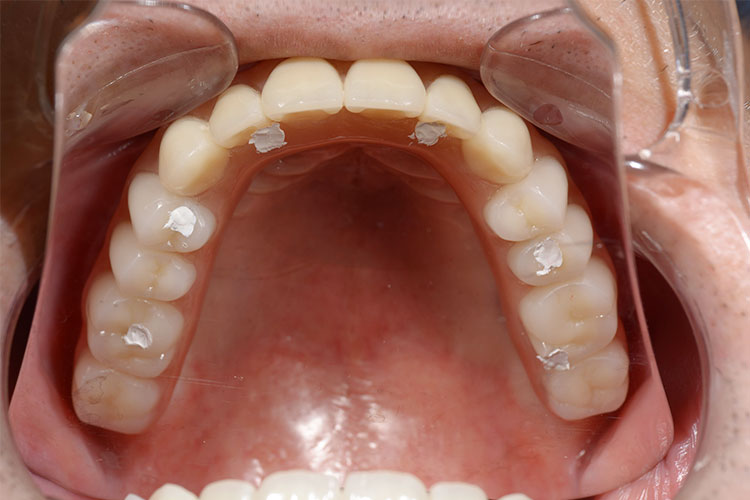

難症例のインプラント治療例【10本】

患者様

情報

治療期間

治療費

埋入数

リスクと副作用

男性

10ヶ月

5,637,600円

10本

術後に痛みや

腫れが出る恐れ